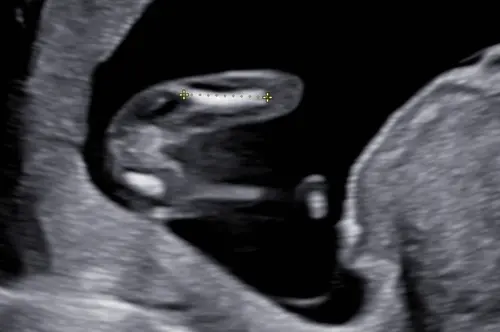

Dit is een echo vanaf de onderkant bij mijn zoon, toen 13 weken echo. Duidelijk twee benen. Mijn zoon was echt heeeeeeel duidelijk een jongen een week of twee na deze echo maar hier dus eigenlijk zo goed als niet zichtbaar

Dit was bij mij met 20 weken, nou zie jij het😂😂😂t was maar goed dat ze het op de achterkant geschreven had